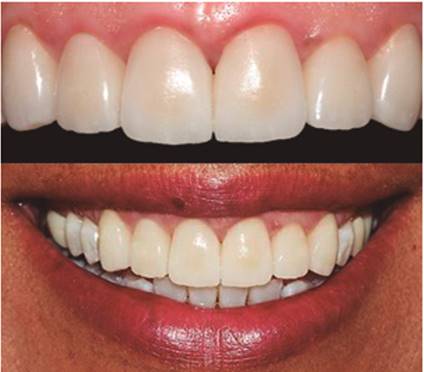

A los siete días (1 septiembre) se realizó retiro de suturas, se observó clínicamente la zona tratada desinflamada, del mismo color de la mucosa adyacente y sin signos de infección (Figura 5a). A las tres semanas de la cirugía se prepararon los dientes y se colocaron los provisionales (Figura 5b) y a las cinco semanas (30 septiembre) se realizó un recontorneo gingival con ayuda de electrobisturí (Figura 6a). A las nueve semanas se observó una adecuada cicatrización y se procedió a hacer toma de impresión (Figura 6b). El 2 de febrero se colocó la restauración final, observando tejidos sanos y estéticos (Figura 7). Mediante el procedimiento quirúrgico se logró la corrección y restablecimiento de los márgenes gingivales según los requerimientos protésicos, se obtuvo además la longitud coronaria deseada en la planeación del diseño de sonrisa. La realización de recontorneo gingival con electrobisturí permitió crear cénits más armoniosos y ayudó a crear mayor simetría en los márgenes gingivales. La paciente expresó sentirse contenta con los resultados finales tanto de la cirugía como de la colocación de las carillas.